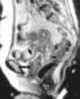

Carcinoma of vagina

Squamous-cell carcinoma of the vagina is a potentially invasive type of cancer that forms in the tissues of the vagina. Though uncommon, squamous-cell cancer of the vagina (SCCV) is the most common type of vaginal cancer. [Source: Wikipedia ]